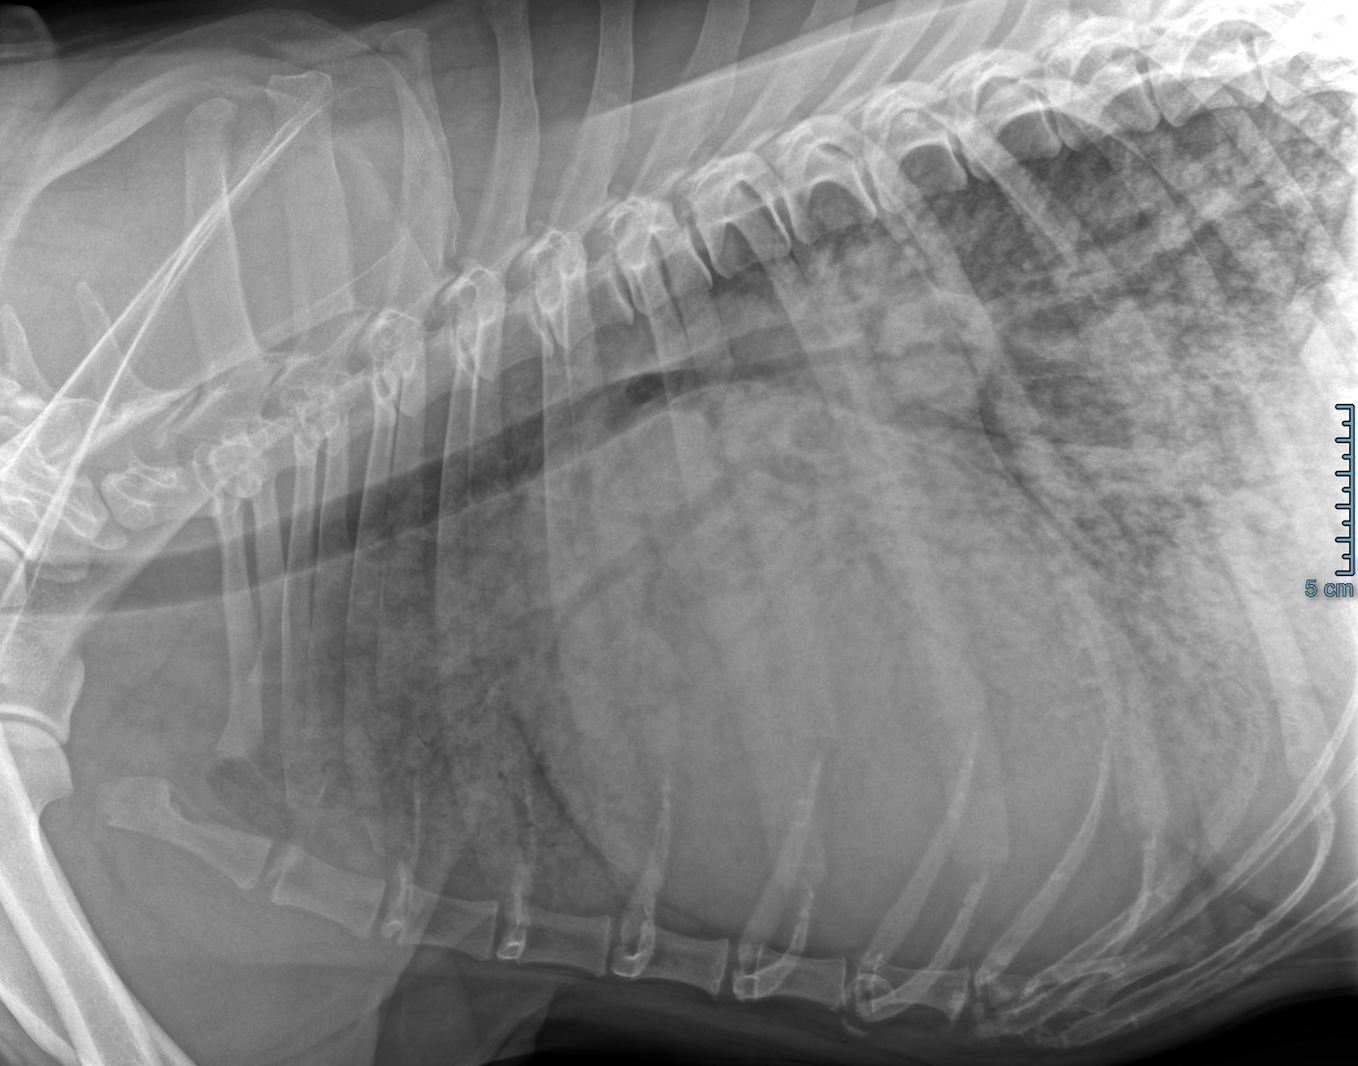

Hunder med hjertesvikt kan også få væskeansamling i buk, rundt lungene og rundt selve hjertet. Ved mistanke om hjertesvikt tar dyrlegen røntgenbilder av brysthulen, eller ultralyd av lungene, for å se etter lungeødem. Ultralydundersøkelse av hjertet utføres av veterinærkardiolog etter at vanndrivende medisiner har hatt god nok effekt til at hunden tåler å ligge på siden. Kardiologen legger en behandlingsplan og skriver ut resept på livsviktige medisiner.